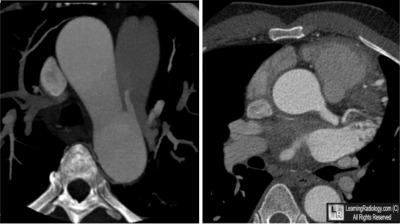

Additional Image-Axial CT Reconstructions through Heart

Axial CT Reconstructions through Heart

5. Patent Ductus Arteriosus

Patent Ductus Arteriosus

- Persistent communication between the thoracic aorta and the pulmonary artery by the ductus arteriosus

- The effect of the left-to-right shunt will depend on the size of the shunt and the pulmonary vascular resistance